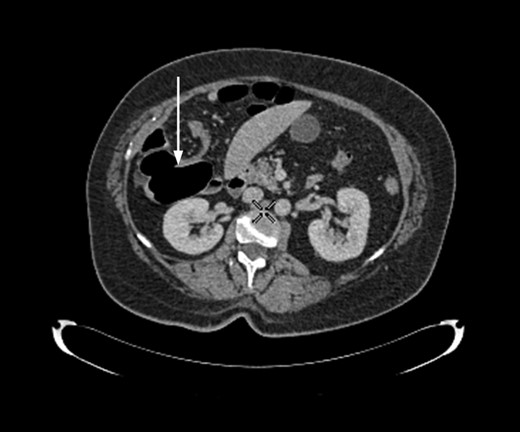

A 58-year-old female with a past medical history of a large intrathoracic hiatus hernia presented to her general practitioner and was subsequently referred to our surgical department with symptoms of sudden onset severe epigastric pain associated with vomiting and abdominal distension. Her abdomen was generally tender, maximally in the epigastric region, although she was not peritonitic. The admission erect chest radiograph showed a large hiatus hernia and an elevated right hemidiaphragm with a large loop of distended bowel (Fig. 1). Subsequent computed tomography (CT) scan demonstrated an almost completely intrathoracic stomach with a degree of volvulus, and the liver medially displaced by a loop of large bowel felt to be caecum (Fig. 2). Since the patient remained otherwise well, bidirectional endoscopy was performed, and given that a volvulus point could not be identified and the ileocaecal junction was not identified, contrast studies were requested (Figs 3–5) which demonstrated an incomplete obstruction caused by a volved caecum rotated anteriorly and cephalad.

Axial section of contrast-enhanced CT demonstrating ‘whirl sign’ at the point of volvulus.